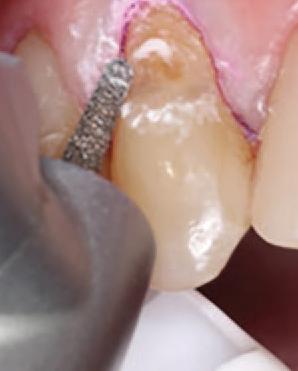

To improve isolation and soft tissue access, a retraction cord was placed before initiating the procedure (Fig. 2). The tooth was evaluated using a caries indicator dye (Kuraray Noritake Dental), helping to identify any remaining infected tissue beneath the dislodged composite (Fig. 3). Decay removal was completed with a diamond bur, and the enamel was bevelled using a starburst pattern to enhance aesthetic blending (Fig. 4). This preparation design was chosen for visual integration rather than bond strength enhancement.

4. Preparation of the lesion completed with diamond bur and starburst beveling pattern to enhance aesthetic blending.